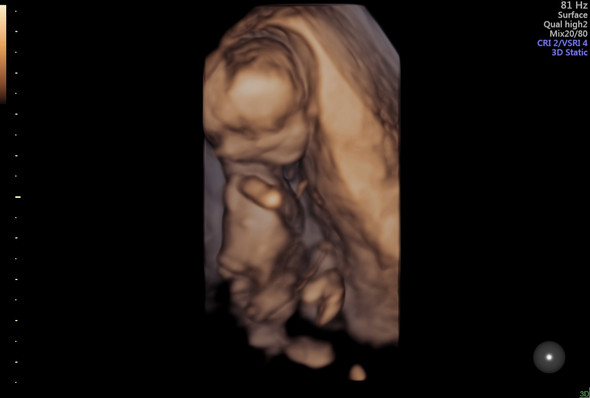

Beim 3DUltraschall, auch 3DSonografie genannt, wird vom Arzt ein Sensor über deinen Bauch geführt, der dein Kind im Mutterleib auf dem Bildschirm sichtbar macht Der Unterschied zum einfachen Ultraschall Die Bilder deines Kindes werden mit einer speziellen Software zu einem dreidimensionalen Bild verarbeitet.

Ein 3DUltraschall gehört nicht mehr zum Rahmen der Vorsorgeuntersuchungen und kann als Zusatzleistung zu den drei üblichen Ultraschallen gesondert in Anspruch genommen werden Er wird nur noch nach medizinischer Indikation von eurem behandelnden Arzt verordnet, der ihn selbst durchführt oder euch an einen entsprechenden Facharzt für.

Ab SSW 15 kann man das Geschlecht des Babys im Ultraschall erkennen Wann wissen wir, ob es ein Mädchen oder ein Junge ist?. Generell ist die 3D und 4D UltraschallUntersuchung so wie die gewöhnliche UltraschallUntersuchung auch unbedenklich Dennoch warnen Experten davor, die 3D und 4D Sonographie ohne medizinische Notwendigkeit durchzuführen Denn die Intensität des 3D Ultraschalls liegt durch die verbesserte Bildgebung deutlich über der Leistung der konventionellen Sonographie. Der Preis eines 3D/4DUltraschallGeräts ist in erster Linie davon abhängig, ob das SonographieGerät nur in einem spezifischen Bereich eingesetzt wird oder für eine breite Palette an medizinischen Anwendungen Die meisten Hersteller bieten UltraschallGeräte mit beiden Funktionen (ab Euro netto) an, sowohl dem 3DUltraschall als auch dem 4DUltraschall.